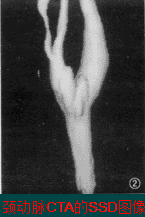

3、表面遮盖(SSD)

SSD是提取组织结构边缘的体素信息,把容积数据转换为一系列多边形表面片拟合的等值面,然后根据光照、明暗模型进行消隐和渲染。

用途:胸腹大血管、肺门及肺内血管、肠系膜血管、肾血管及骨与关节的三维显示。

缺点:容易造成虚假显示或显示面上产生空洞,且无法显示数据体内部的细节信息。